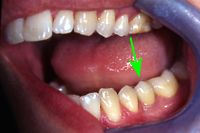

Eine Frenektomie ist eine Lippenbändchen-Durchtrennung, welche oft vor kieferorthopädischen Eingriffen, manchmal aber auch bei extremer Ausprägung des Lippenbändchens nötig wird. Ein solches stark ausgeprägtes Lippenbändchen (Abb. 9) wurde bei einem 8 Jahre alten Kind mittels Laser durchgeführt (Abb. 10). Das Resultat direkt nach dem Eingriff (Abb. 11) zeigt sichtbar den minimalinvasiven Charakter der Behandlung mit dem Laser.

Das Vestibulum befindet sich zwischen den Wangen und den Zahnreihen. Ein Patient leidet an einem sehr tiefen Vestibulum auf der rechten Seite (Abb. 12). Mittels Laser-Zahnmedizin kann eine minimalinvasive Korrektur durchgeführt werden, bei der ein Teil des Vestibulums entfernt wird. Das Resultat 8 Tage nach der Operation ist sehr befriedigend (Abb. 13).

Die untere Bildserie beschreibt die Entfernung eines Hämangioms auf der Unterlippe eines 72 Jahre alten Patienten. Ein Hämangiom (Blutschwämmchen) ist ein embryonaler Tumor mit Endothelproliferation und sekundärer Ausbildung von Gefässlumen. Ein Herausschneiden war bei der gegebenen Grösse notwendig. Durch das Alter des Patienten und durch die empfindliche Lokalität des Hämangioms an der Lippe ist ein minimalinvasiver Eingriff mit schneller Wundheilung essentiell. Dies wird durch eine Laserbehandlung garantiert (Abb. 14-16).